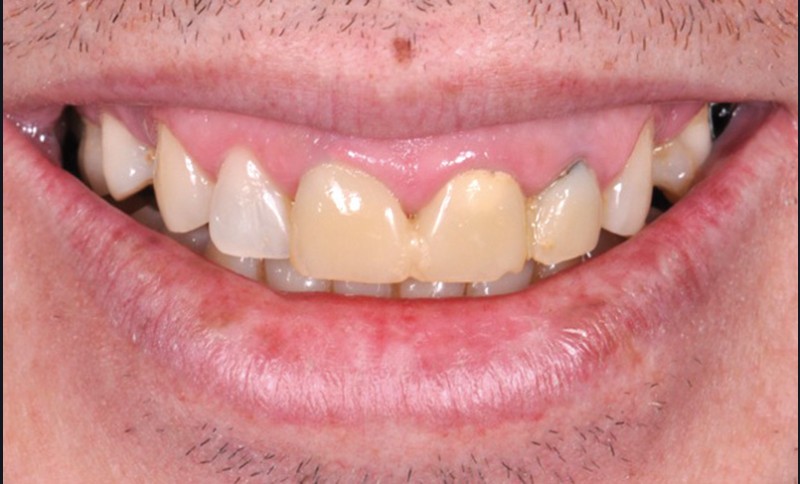

Dans la zone antérieure maxillaire, l’approche esthétique du diagnostic est essentielle (fig. 2a). En effet, la première impression d’un individu est souvent fondée sur ce que l’on perçoit de son visage. Le regard et le sourire constituent les deux pôles attractifs de ce dernier. À distance sociale (et non au fauteuil), ils focalisent toute notre attention et communiquent tous les types d’émotions, verbales et non verbales, de notre interlocuteur. À ce titre, le sourire et le rire représentent la première exposition de l’esthétique dentaire au sein du visage. L’harmonie du sourire est toujours plaisante si l’ensemble des compositions, labiales, dentaires et gingivales, sont agréables au sein du visage des patients.

De nombreuses circonstances nuisent à l’harmonie dento-gingivale des arcades dentaires lors du sourire et représentent un véritable défi esthétique (fig. 2a).